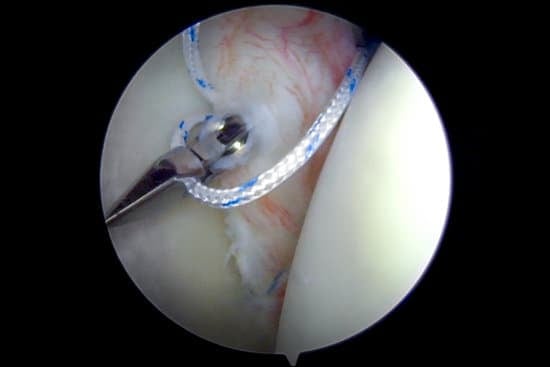

3. 반카르트 수술: 관절경 봉합술

2) 수술 과정

관절경 삽입: 내시경을 이용해 어깨 내부를 확인합니다.

와순 봉합 및 고정:

앵커(Anchor)를 이용해 찢어진 와순을 뼈에 고정합니다.

수술 후 마무리: 봉합 부위를 정리하고 절개 부위를 닫습니다.